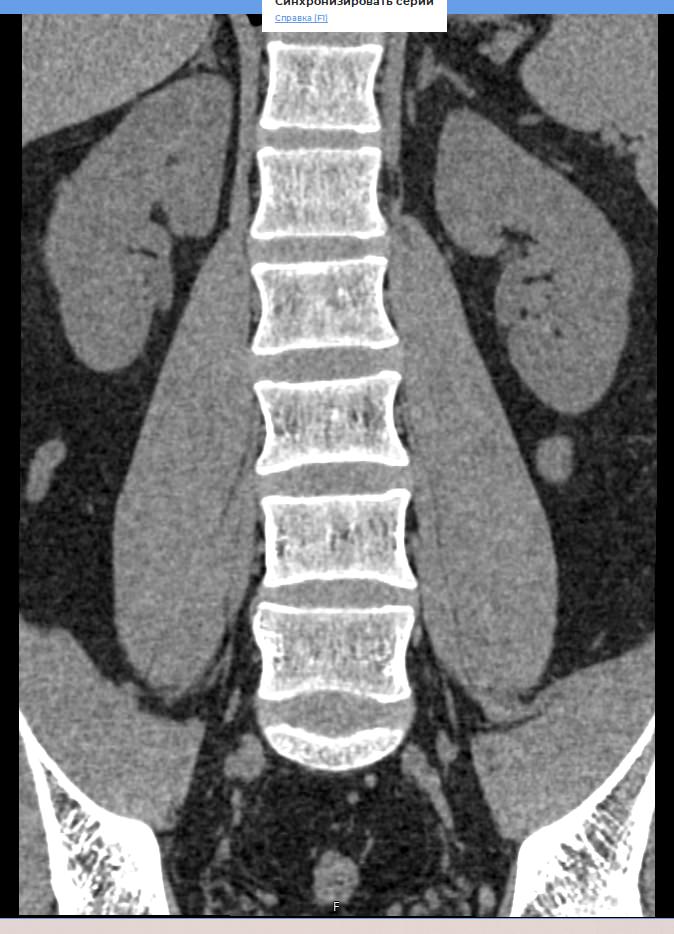

Мультиспиральная компьютерная томография является наиболее точным и информативным методом диагностики различных заболеваний позвоночника и, в частности, пояснично-крестцового отдела. Сканирование проводится при помощи рентгеновского излучения, в результате чего получают серию послойных изображений пояснично-крестцового отдела позвоночника.

В медицинских центрах «Доступная медицина» обследование пояснично-крестцового отдела позвоночника осуществляется на современных мультиспиральных компьютерных томографах последнего поколения TOSHIBA AQUILION в модификациях, позволяющих выполнять одномоментно 64 и 128 срезов анатомической зоны для получения снимков высокого разрешения. Послойное сканирование исследуемой области проводится с минимальной толщиной среза от 0,5 мм, что обеспечивает получение изображений органов в мельчайших подробностях.

Инновационные компьютерные приложения позволяют построить 3D-модель исследуемого органа, обеспечивая детальную визуализацию строения внутренних структур позвонков, хрящевых элементов, кровеносных сосудов и окружающих тканей.

- изгиб позвоночного столба (поясничный лордоз нормальный, усилен или сглажен);

- не смещены ли позвонки относительно друг друга;

- нет ли признаков костной деструкции, остеопороза;

- нормальная ли высота тел позвонков;

- нет ли грыж (протрузий, экструзий), и если есть – где они находятся, на сколько миллиметров выступают в просвет позвоночного канала, какие анатомические структуры сдавливают;

- дегенеративно-дистрофические изменения: спондилез, спондилоартроз, остеохондроз;

- стеноз (сужение) позвоночного канала;

- патологические изгибы позвоночника.